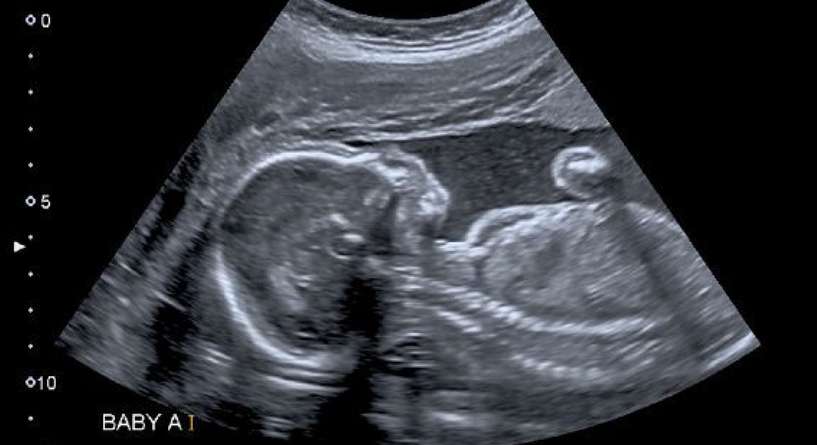

اكتشفي معنا هل ممكن يتغير نوع الجنين بعد الشهر السادس وفي حال كان هذا الامر ممكنا اذا ما هو السبب الرئيسي الذي من شانه ان يؤدي الى هذا الخطا.

بالعادة، يتم تحديد نوع الجنين خلال الشهر الرابع من الحمل من خلال الخضوع لفحص بالموجات فوق الصوتية وخلال هذه الفترة يمكنك أن تعلمي إذا كنت حامل ببنت أن صبي. لكن من المستحيل أن يتغير نوع الجنين خلال الشهر السادس. لذلك، في حال تبين مع الطبيب في الشهر الرابع أنك حامل ببنت وصرّح بعد شهرين أنك حامل بصبي إذاً هذا يكون خطأ قد قام به الطبيب في طريقة قراءة الفحص أم أن أعضاء الجنين التناسلية لم تكن واضحة تماماً خلال الفترة الماضية.